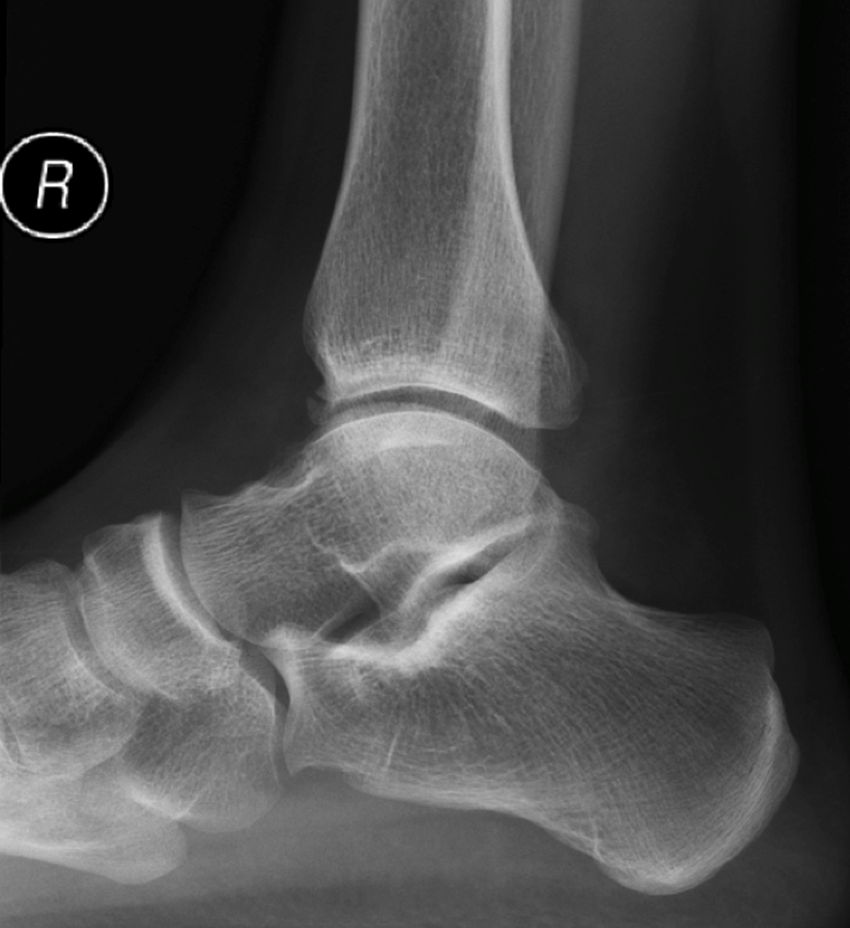

Geralmente o estudo é complementado com exames auxiliares de diagnóstico, como a radiografias em carga (pode logo identificar os osteófitos), ecografia e/ou a ressonância magnética.